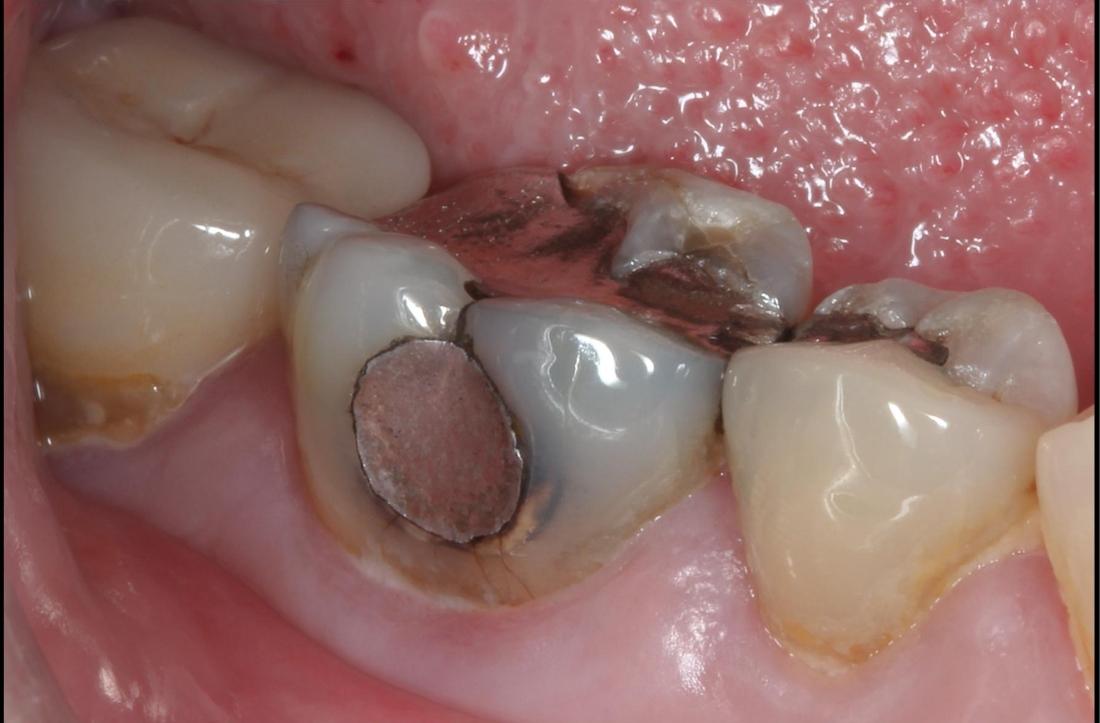

Large amalgam fillings very often lead to the fracturing of teeth over time. This tooth had a large amalgam filling which had begun to leak, allowing bacteria to enter and cause decay. It also had a fractured cusp and several other developing fractures. If left untreated, further breakdown would have lead to toothache and possibly the need for extraction. Here a crown was placed, giving it a new hard wearing outer shell that will prolong the life of this tooth.